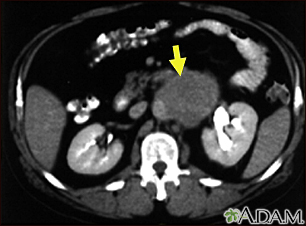

Lymph node metastases, CT scan